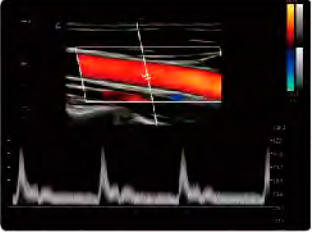

L'échographe parvient à améliorer les performances de ses concurrents en termes d'innovation. Il améliore la flexibilité et le flux de travail en contenant des fonctions telles que l'imagerie tissulaire Doppler continue, CW, TDI et les calculs IMT automatiques. De plus, l' échographe Chison CBit 6 est équipé d'une large gamme de sondes qui prennent en charge des technologies innovantes et s'adaptent aux besoins de tout professionnel de la santé.

- Ajuste automatiquement la direction ROI et le PFR en mode couleur et l'entrée Doppler en mode PW

- Gain de temps, efficacité